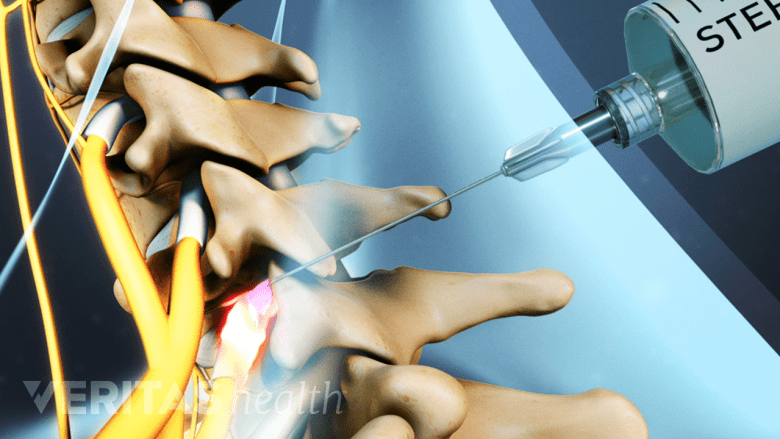

Nerve block injections are used to identify the origin of pain in the cervical spine.

Diagnostic nerve block injections are used to test the exact source of pain in the cervical spine. The technique involves injecting a pain-relieving anesthetic or anti-inflammatory solution around the nerve/joint. Medical imaging such as fluoroscopy (x-ray guidance) accompanied by contrast is used to guide the needle to the correct spot. Pain relief from these injections may be seen in all areas innervated by the nerve, including regions in the head.